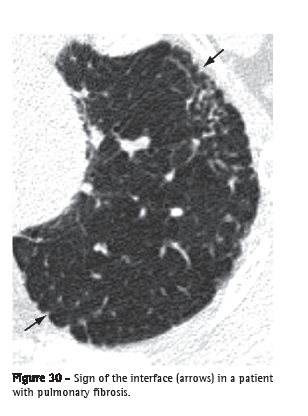

Interface (interface)

An interface is the separation between two structures or spaces. When two thoracic structures with different radiological densities are juxtaposed, their boundaries are clear. For example, vessels presenting soft tissue density coming into contact with the air density of the surrounding ventilated lung. The "sign of the interface" defines the irregularity of the margins of different intrathoracic structures, such as vessels, bronchi and pleural surfaces, generally resulting from interstitial disease that causes fibrosis (Figure 30).(3)